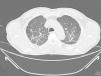

Presentamos el caso clínico de un hombre de 60 años, fumador activo (con una dosis total acumulada de 5 paquetes/año), que consulta por dolor torácico de características pleuríticas y tos seca. Tiene hipertensión arterial en tratamiento con nimodipino y enfermedad cerebro-vascular antigua. En la exploración física destaca la presencia de hipoventilación en la auscultación respiratoria. En el análisis sanguíneo se objetivó una gamma-glutamil transpeptidasa de 203 UI/L, alanina aminotransferasa de 242 UI/L, con valores de bilirrubina normales. La radiografía de tórax presenta un patrón intersticial bilateral de predomino en lóbulos superiores. La tomografía computarizada de alta resolución de tórax muestra adenopatía axilar derecha de 1,2cm, adenopatías mediastínicas menores a 1cm, algunas de ellas calcificadas en localización hiliar bilateral y subcarinales y aumento de la densidad en vidrio deslustrado con engrosamiento del intersticio peribroncovascular de morfología micronodular bilateral y difuso (fig. 1). La curva flujo volumen y la pletismografía no muestran alteraciones. La difusión de monóxido de carbono fue del 87% y corregido por volumen alveolar de 76%. Se realizó una fibrobroncoscopia que no detectó alteraciones en el árbol bronquial. El lavado broncoalveolar objetivó una celularidad de 88% de macrófagos, 8% linfocitos, y 2% eosinófilos. Población linfocitaria CD4 78%, CD8 6%; 3% de linfocitos en las muestras analizadas de CD4. Los estudios microbiológicos fueron negativos. Las biopsias transbronquiales mostraron una neumonitis de patrón intersticial con infiltrado inflamatorio, que expande el intersticio y que en algunas áreas forma lesiones granulomatosas constituidas por histiocitos epitelioides que se acompañaban de células gigantes tipo cuerpo extraño, algunos de los cuales confluyen sin necrosis central y son de distribución peribronquiolar y perivascular sin imágenes de vasculitis. Todo ello compatible con inflamación granulomatosa no necrotizante sugestiva de sarcoidosis pulmonar. Se completó el estudio con una ecografía abdominal, donde se observó un aumento difuso de la ecogenicidad hepática y con marcadores de autoinmunidad que detectaron títulos elevados de anticuerpos antinucleares (mayor de 1/160) y antimitocondriales tipo M2 (mayor de 1/320).